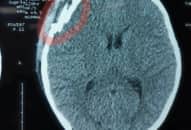

Bé 8 tuổi ở Quảng Bình đang chơi trong quán thì bị một thanh niên say xỉn cầm chai bia đập vào đầu.

Hình ảnh chụp CT cho thấy trẻ bị vỡ xương sọ.